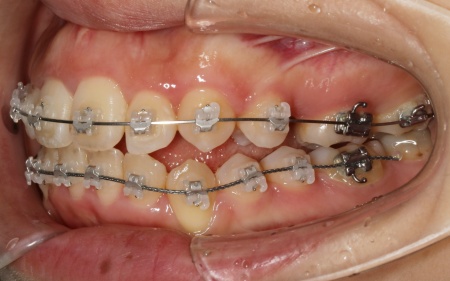

続いて、上下の歯の表面に金属のブラケットよりも目立ちにくい「セラミックブラケット」を接着し、ワイヤー矯正を開始しました。

ワイヤー矯正である程度歯並びが整ったら、マウスピース矯正に移行します。